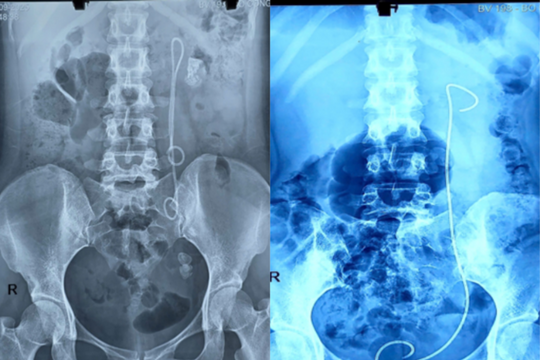

Nữ bệnh nhân bị bỏ quên thiết bị y tế trong cơ thể suốt 15 năm